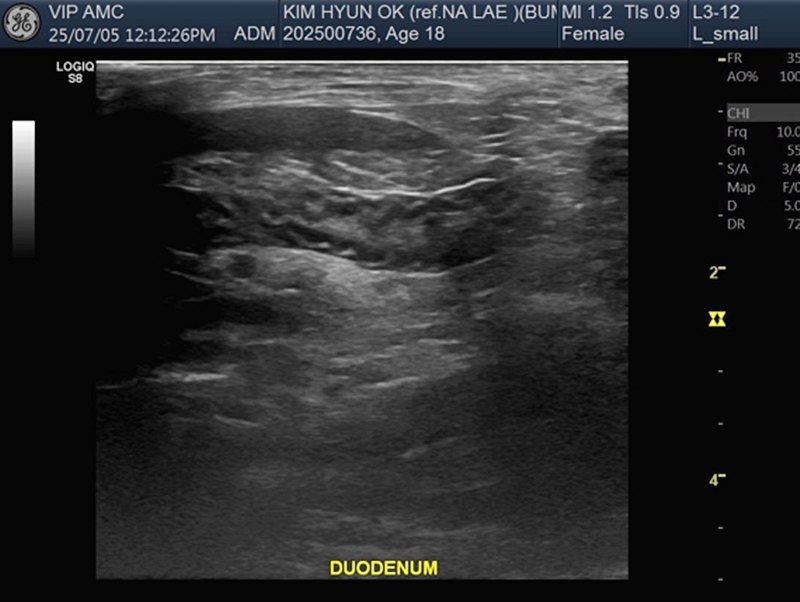

혈액검사에서는 갑상선호르몬을 의미하는 T4, fT4의 상승, 간수치의 경미한 상승이 확인되었습니다. 초음파 검사에서는 위장관염과 만성신장질환 소견이 발견되었습니다. ▼